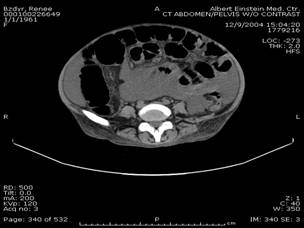

Normal epiploic appendages